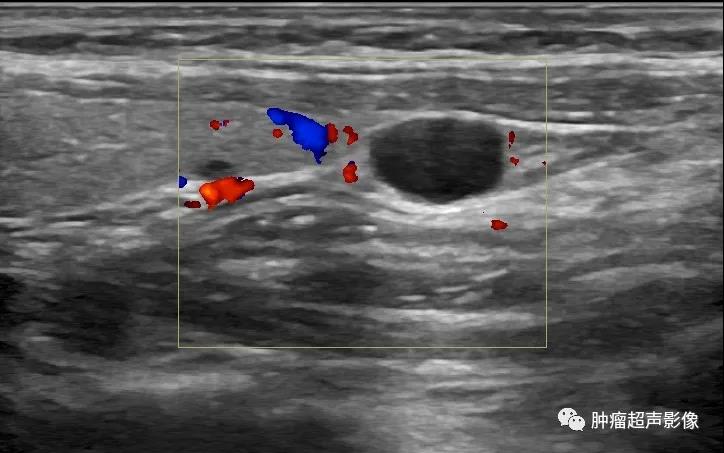

5、由于囊壁菲薄,CDFI壁上及内部无血流,但是可观察其与甲状腺上下动脉的关系,辅助判断位置。

甲状旁腺囊肿:甲状腺左侧叶下极旁见边界清的无回声,椭圆形,与甲状腺组织无关,囊壁薄而光滑,透声佳,无血流。